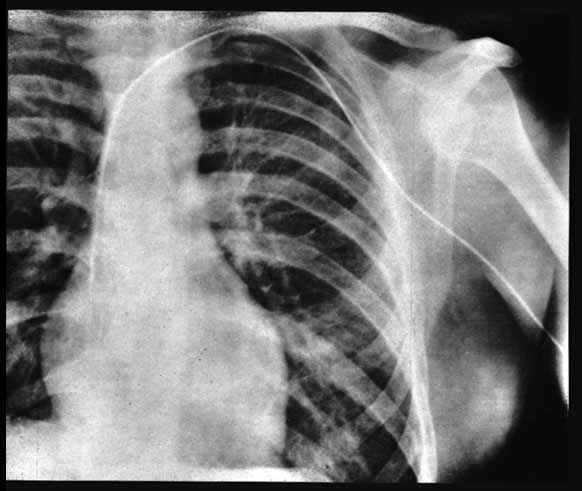

Caminhou calmamente até a sala de radiologia e, com a ajuda de um técnico, tirou uma radiografia que mostrava o cateter dentro do átrio direito.